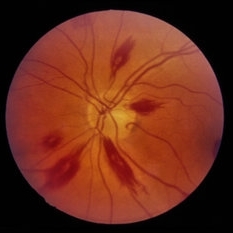

Roth Spots and Retinal Hemorrhage

This fundus photograph of the left eye displays Roth spots with pre, intra, and subretinal hemorrhage. Roth spots are characteristic lesions that may appear in thrombocytopenic patients. This particular patient has acute myeloid leukemia and is post-chemotherapy which may lead to a decrease in red blood cell and platelet counts.